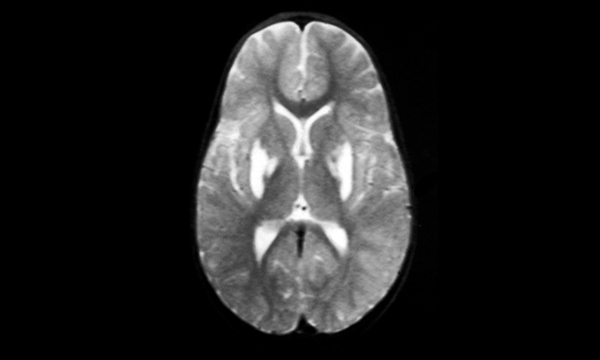

Pfeiffer syndrome is a genetic condition thought to occur once in every 100,000 people